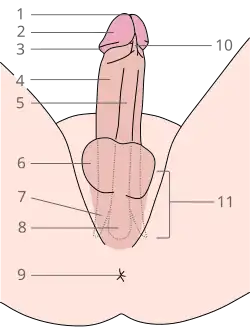

2 Glande

3 Coroa

4 Corpo cavernoso

5 Corpo esponjoso

6 Escroto

7 Crus do pênis

8 Bulbo do pênis

9 Ânus

10 Frênulo prepucial

11 Raiz do pênis.

O pénis humano é formado por três colunas de tecido: dois corpos cavernosos situam-se lado a lado no lado dorsal e um corpo esponjoso entre eles no lado ventral.[11]

A extremidade alargada e em forma de bulbo do corpo esponjoso forma a glande do pénis com dois tipos específicos de sinusóides, que sustentam o prepúcio, uma prega de pele solta que em adultos pode retrair para expor a glande.[12] A área no lado inferior do pénis, onde o prepúcio é ligado, é chamado o frênulo prepucial. A base arredondada da glande é chamada de coroa. As glândulas Prepuciais, situadas na coroa, secretam substâncias que compõem a secreção esbranquiçada que recobre o pênis, o esmegma.[13] A rafe perineal é a linha perceptível ao longo da parte inferior do pénis.

A rafe perineal é a crista visível entre as metades laterais do pénis, encontrada na parte ventral ou inferior do pénis, indo do meato (abertura da uretra) através do escroto até o períneo (área entre o escroto e o ânus).[14]